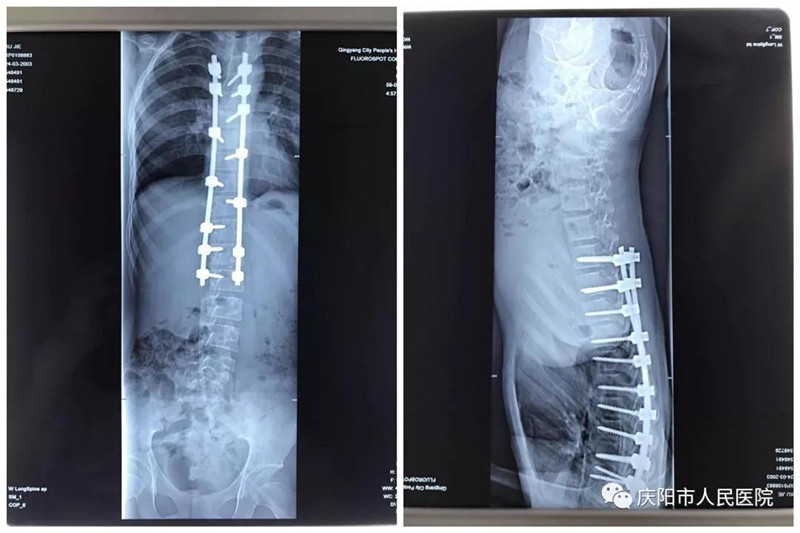

特发性脊柱侧凸畸形矫形手术成功实施。脊柱侧凸俗称脊柱侧弯,是一种脊柱的三维畸形,包括冠状位、矢状位和轴位上的序列异常,这是继脊柱后凸畸形矫形手术开展以来,我院骨一科在脊柱外科领域的又一项成就,标志着我院脊柱外科技术又向前迈进了一步。